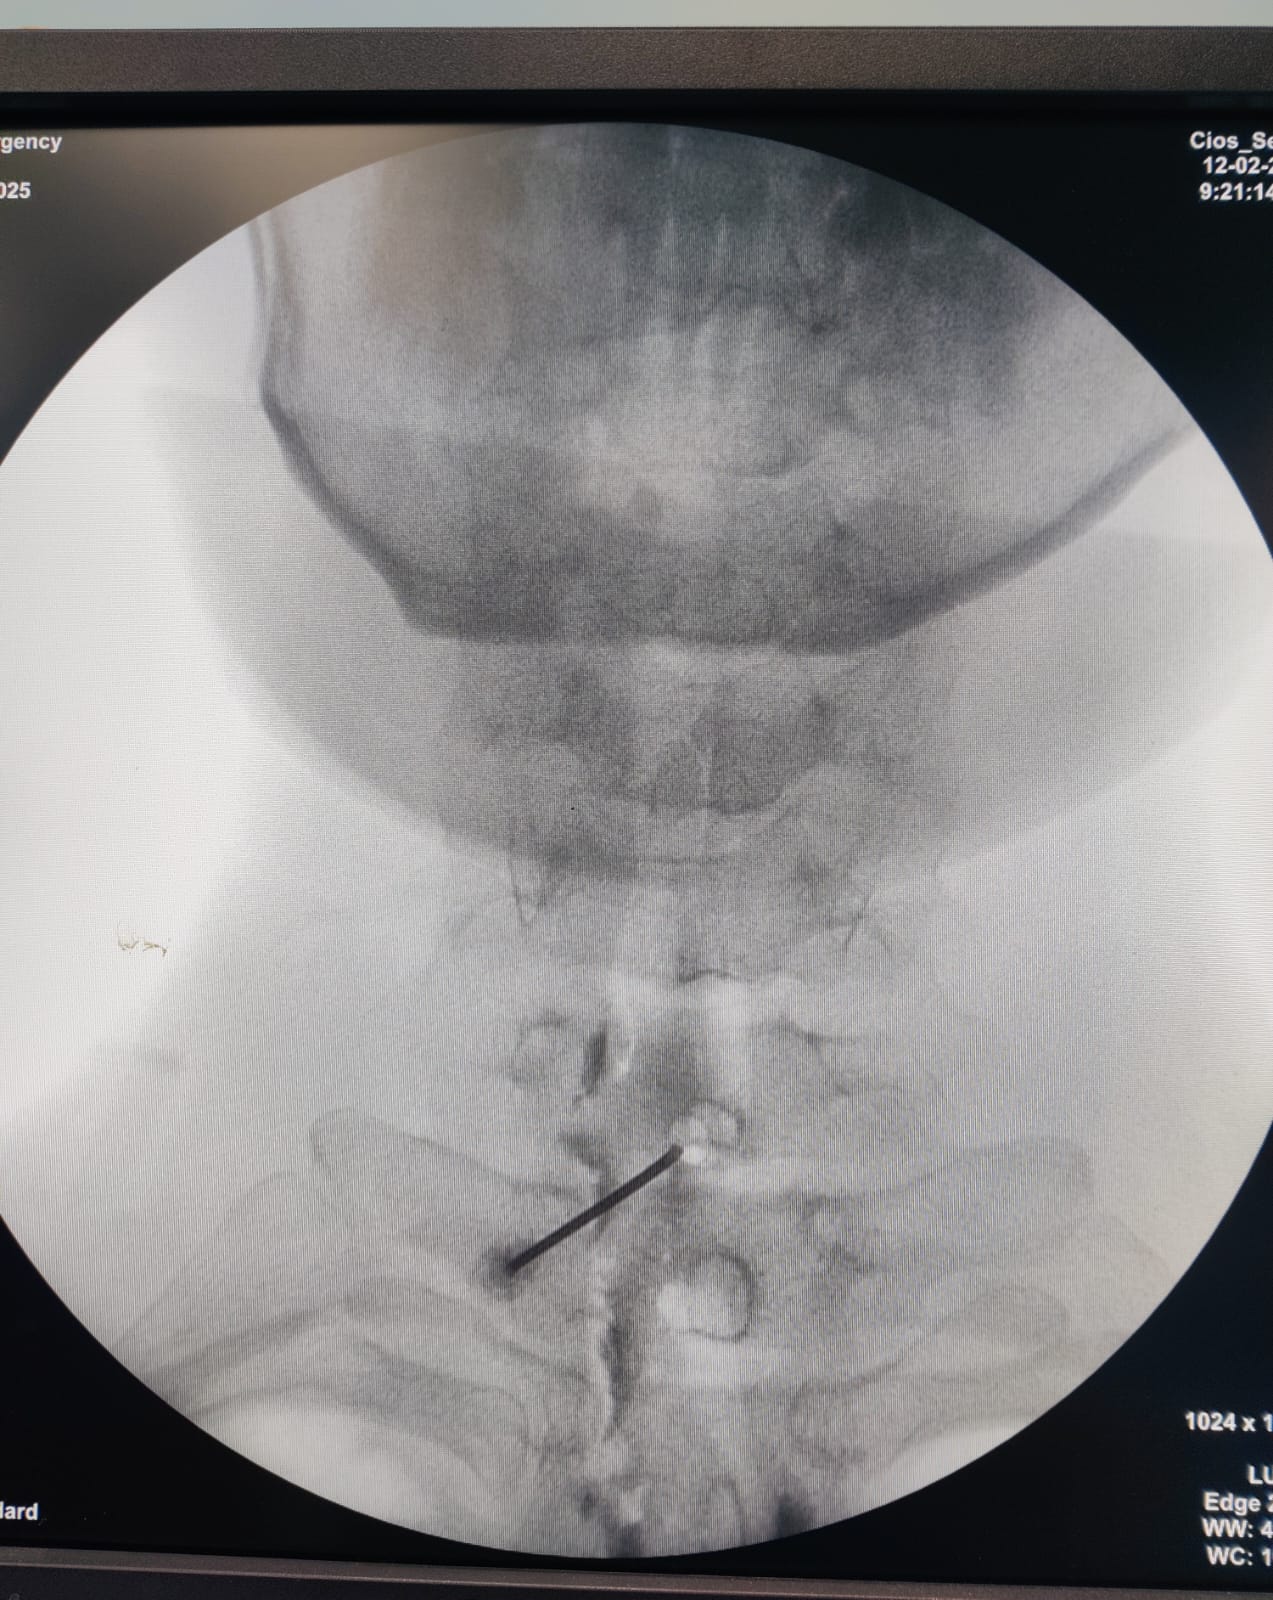

When to Consider a Cervical Epidural Injection? Cervical epidural steroid injections are an effective treatment option for patients suffering from chronic neck pain, cervical radiculopathy, disc herniation, and spinal stenosis. This procedure is particularly beneficial for individuals experiencing persistent neck pain radiating to the arms, tingling, numbness, or weakness due to nerve compression. πŸ‘‰ Dr. Priya Rathi, the best spine and pain specialist, is an expert in performing cervical epidural injections with precision and care. She ensures optimal pain relief by combining this procedure with USG-guided dry needling to address the muscular component, providing long-term results. If you are struggling with chronic neck pain, consult Dr. Priya Rathi for a comprehensive and advanced pain management approach! βœ…